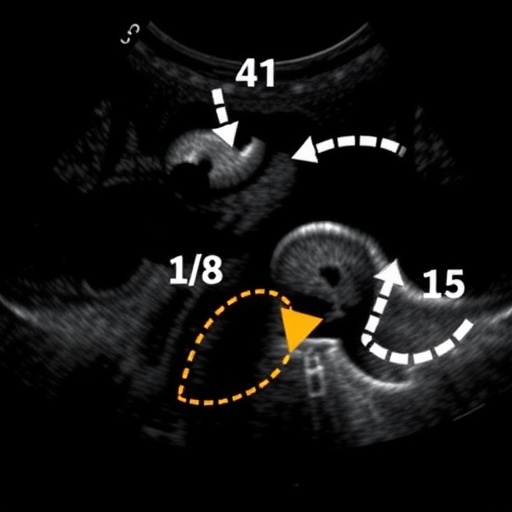

In this comprehensive retrospective investigation, a cohort of 86 patients presenting with a total of 89 testicular lesions underwent thorough evaluation with conventional ultrasound and texture analysis between February 2017 and June 2021. These patients were stratified into four distinct groups based on histopathological confirmation: epidermoid cysts, sertoli-leydig cell tumors, lymphomas, and malignant germ cell tumors. This stratification enabled a rigorous comparative analysis between imaging diagnoses and gold-standard pathological findings.

The results illuminated the limitations of conventional ultrasound alone, with sensitivity rates for detecting sertoli-leydig cell tumors and epidermoid cysts languishing at 40% and 22.2%, respectively. Similarly, lymphoma and malignant germ cell tumor detection rates were 15.8% and 19.0%, underscoring the pressing need for improved diagnostic methodologies. While specificities remained high, the low sensitivity of conventional ultrasound resulted in suboptimal diagnostic confidence and potential overtreatment.

The study’s focal innovation revolves around the application of nine quantitative texture feature parameters—minimum gray, maximum gray, standard deviation, skewness, contrast, sum average, difference variance, difference entropy, and dissimilarity—combined with patient age and tumor size metrics in a sophisticated binary logistic regression model. This multifactorial approach quantified the likelihood of each pathological classification, allowing for a nuancical diagnostic insight surpassing traditional methodologies.

Notably, receiver operating characteristic (ROC) analyses demonstrated remarkable diagnostic performance using this combined model. The area under the curve (AUC) values approached near perfection for several tumor types: 0.992 for sertoli-leydig cell tumors, 0.970 for epidermoid cysts, and 0.971 for lymphomas. Even malignant germ cell tumors, traditionally challenging to diagnose, achieved a commendable AUC of 0.809. Such robust discriminatory power translates into sensitivity and specificity rates exceeding 90% for most tumor categories when assessed by the joint diagnostic model.